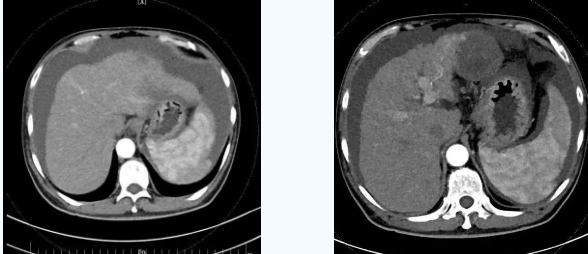

術(shù)后一個(gè)月秦先生來院復(fù)查,腹水已明顯較前減少,精神和飲食較術(shù)前明顯好轉(zhuǎn)。

韓國宏院長介紹,TIPS原理是采用特殊的介入治療器械,在X線透視導(dǎo)引下,經(jīng)頸靜脈入路,建立肝內(nèi)的位于肝靜脈及門靜脈主要分支之間的人工分流通道,并以金屬覆膜內(nèi)支架維持其永久性通暢,達(dá)到降低門脈高壓后減少腹水產(chǎn)生,控制和預(yù)防食道胃底靜脈曲張破裂出血的目的。